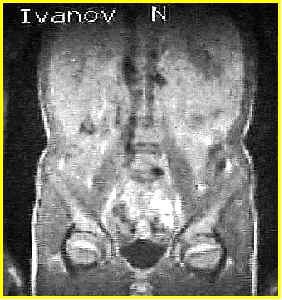

МР томограмма.

Вариант нормы.